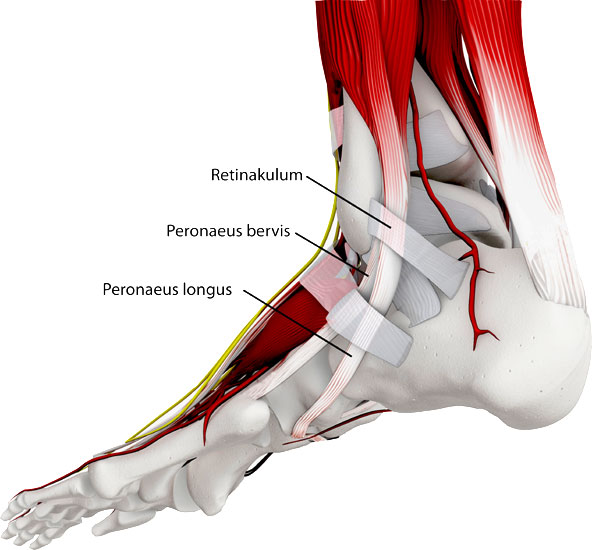

Der anatomische Verlauf der Peronealsehnen spielt bei den meisten Erkrankungen eine zentrale Rolle.

Die Peroneus longus Sehne und die Peroneus brevis Sehne (wenn vorhanden auch die Peroneus quartus Sehne) verlaufen hinter der Fibula, um dann um die Außenknöchelspitze herum nach ventral zu ziehen. Die Länge des Muskels unterliegt einer großen anatomischen Variation, teilweise sind der Sehne noch distal der Fibulaspitze Muskelanteile angelagert. Zur Vermeidung einer Luxation über den Malleolus lateralis, gleiten die Sehnen in einer muldenförmigen Rinne im Bereich der dorsalen Fibula, zusätzlich werden die Sehnen durch das Retinaculum superior und das Retinaculum inferior stabilisiert 1.

Querschnitt der Peronealsehnen in Höhe des Sprunggelenks.

Horizontal betrachtet liegt die Peroneus brevis Sehne der Fibulagleitfläche auf. Die Peroneus brevis Sehne hat einen halbmondförmigen Querschnitt. Auf dieser wiederum liegt die Peroneus longus Sehne.